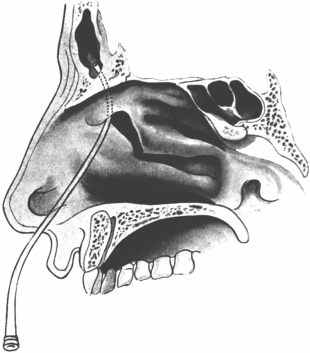

| 345. | Catheterizing the Sphenoidal Sinus | 654 |